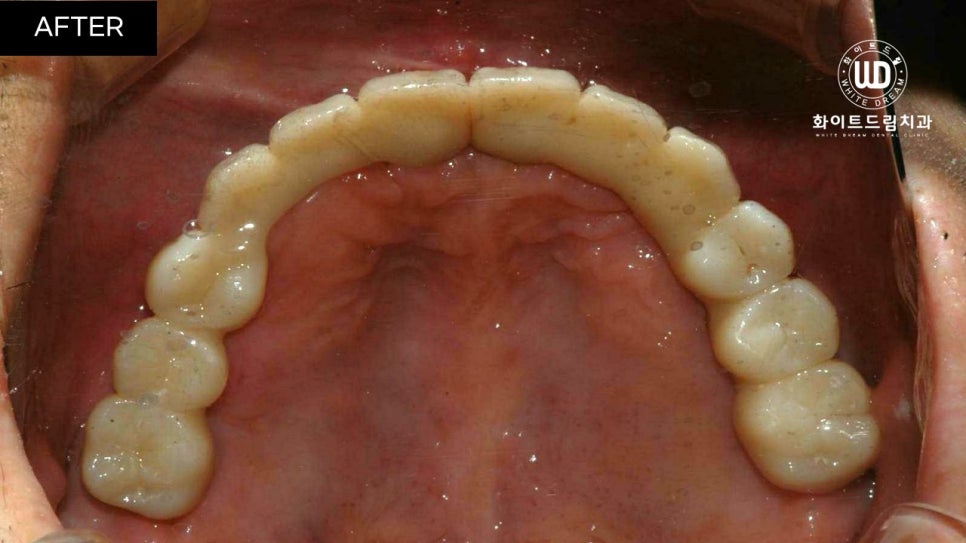

중간 지주대를 픽스처에 연결해주고 2주뒤 최종 보철물까지 올려주니 실제 치아와 비슷하게 기능적, 심미적으로 회복되었습니다.

진행한 치료 기간은 22년 6월부터 22년 12월까지 약 6개월 정도 소요되었습니다.

상악 2번 하악 1번 총 3번에 걸쳐 상악동 거상술과 뼈이식을 동반한 임플란트 식립을 진행했습니다. 그 후, 5개월 뒤 임플란트 보철 인상채득 후 2주 뒤에 보철을 마무리 해드렸습니다.

치아 정면 전/후 사진을 함께 살펴보면, 임플란트 식립 모양이 돔 형태로 예쁘게 이식된 것을 확인할 수 있습니다. 전체 임플란트는 교합면을 잘 선정하는 것이 중요합니다. 교합면은 자연치가 맞물리는 면으로, 너무 높으면 턱관절에 무리가 갈 수 있고 저작할 때 고르게 분산되지 않습니다.

반대로 너무 낮으면 구강 내부 혀나 볼을 씹어 상처가 나고, 턱 모양에도 영향을 끼칠 수 있기 때문에 정밀 검사 후 적절하게 식립하는 것이 좋습니다.

환자분께서 아직 젊은 나이임에도 불구하고 좋지 않은 치아상태로 인하여 자신감이 많이 하락하신 상태였는데, 씹는 힘은 물론 외적인 모습까지 복구가 되어 만족스러운 결과를 얻으셨습니다.

전체발치 및 전체 임플란트 식립은 사후관리가 필수인데, 현재까지 큰 불편함 없이 잘 사용하고 있다고 하셨으며, 정기적으로 검진 또한 잊지 않고 관리해주고 계십니다.